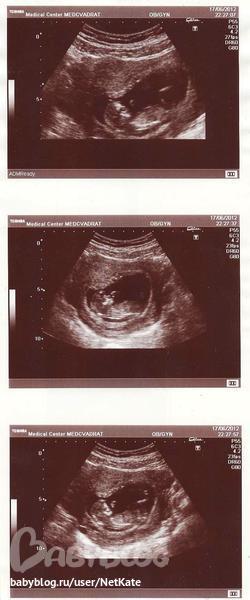

Первый скрининг

Результаты: УЗИ, КТГ, доплера, скринингаСегодня с утра были с мужем на 1 скрининге. Сделали УЗИ - завтра нам 12 неделек. Сидит там себе наш малышок, к нам правым бочком, болтает во все стороны ручками и ножками, и даже стал сосать большой пальчик - видимо, почувствовал внимание "публики"))) Такой зайкин!

Сердецебиение 150 ударов, как и в прошлый раз, КТР 50 мм, БПР 21 мм, толщина воротникового пространства 1.7 мм (Г сказала, нет синдрома Дауна и т.п. пороков), носовая кость визуализируется. 4-х камерный срез сердца - норма. Размеры плода соответствуют 11 неделям 6 дням.

Результат: врожденных пороков не обнаружено. Ура!!

P.S. 3 фото малыша (в т.ч. сосущего пальчик), как и обещала, выкладываю после отпуска))